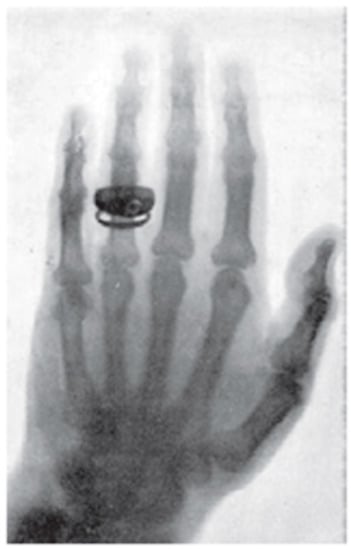

According to Roentgen’s will, all his diaries and notes were destroyed after his death which resulted in a great loss of vital information for historians, such as the exact date when Roentgen realized the importance of the penetrating power of this new ray. From a letter written by his wife Anna Bertha Ludwig in March 1896 to one of his cousins Mrs. L.R. Grauel of Indianapolis, it was found that Roentgen first noticed this new radiation some time in November 1895 [4]. As Bertha mentioned in her letter, on an evening of November 1895 she became angry with her husband for the quality of food. In order to soothe her, Roentgen took her downstairs to his laboratory and introduced her to the mysterious new rays. However, it was not mentioned whether her hand with a ring was exposed to this ray (Figure 2) on the same day. According to Edgar Ashworth Underwood, Director of Wellcome Historical Museum, the picture of his wife’s hand was taken on 8 November 1895. This date was accepted by Konrad Weiss, the historiographer of Austrian Roentgen Society and is accepted as the date of the discovery.

Figure 2.

X-ray picture taken by Roentgen of his wife Bertha Ludwig’s hand. (Courtesy: Prof. Alok Mukherjee, Jadavpur University, Kolkata, India).